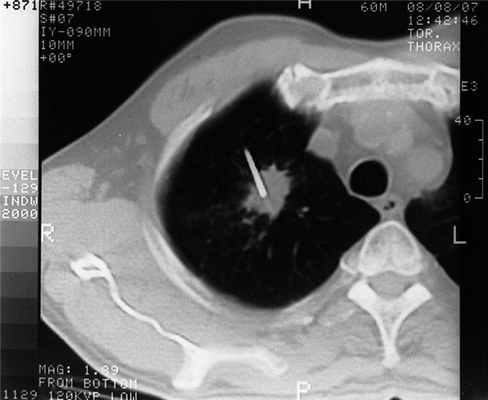

При проведении трансторакальной биопсии легкого получить материал для дальнейшего исследования удалось у 103 пациентов. В 4 наблюдениях проведение пункции оказалось неудачным и морфологический материал не был получен по причине развившегося пневмоторакса (3 наблюдания), не позволившего локализовать иглу в опухоли, и в связи с плотной консистенцией опухоли и ее малым размером (1). Процедура пункции вместе с предварительной КТ-разметкой занимала от 15 до 35 мин. Как правило, для локализации иглы в опухоли было достаточно одного прокола грудной стенки (рис. 2), Рисунок 2. Компьютерная томограмма больного С. Конец иглы локализован в центре опухоли правого легкого. в редких наблюдениях эта процедура осуществлялась повторно.

Трепанационная биопсия была выполнена 69 больным (рис. 3). Рисунок 3. Компьютерная томограмма больной С. На срезе видны две части иглы: троакар у переднего полюса опухоли и проведенный через него стилет с расщепленным концом в центре опухоли. Окончательный диагноз в 57 наблюдениях был представлен злокачественными опухолями. В 53 из них по результатам морфологического исследования правильно верифицировано заболевание (в 83,9% - гистологически, в 76,8% - цитологически). Чувствительность трепанационной биопсии для верификации злокачественного процесса составила 93%. Из 13 больных с неопухолевыми образованиями легких у 12 правильно верифицирован диагноз. Таким образом, точность трепанационной биопсии составила 94,2%. Осложнения наблюдались у 10 (14,5%) больных: пневмоторакс - у 8, кровохарканье - у 2. Клинически значимые осложнения, потребовавшие вмешательства и медикаментозной коррекции, развились в 2 наблюдениях (дренирование плевральной полости, гемостатическая терапия). Отмечено, что при проведении трепанационной биопсии осложнения были более тяжелыми, это вполне соответствует данным литературы, свидетельствующим об увеличении частоты пневмотораксов при использовании игл большего диаметра [3, 8]. По полученному гистологическому материалу 5 больным раком легкого выполнено исследование опухоли на наличие мутации EGFR, что в значительной степени повлияло на тактику лечения.